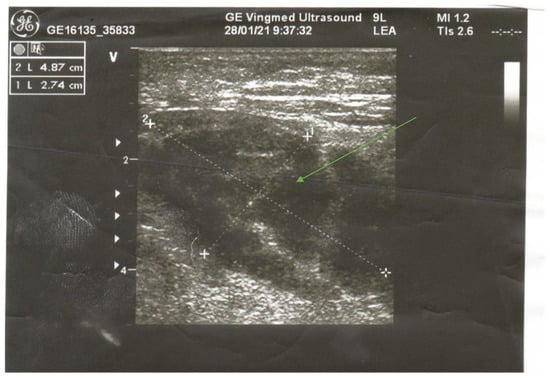

In a physical examination, we found a painful and swollen area on palpation. There was no erythema, warmth, or any other changes on the overlying skin. There were no signs of critical limb ischemia, and the pulse was palpable on both lower extremities. Doppler ultrasound (USG) was performed, which excluded vein thrombosis or leg ischemia. USG revealed a hypoechogenic oval structure sized 4.87 × 2.74 cm (Figure 1). We observed a small blood vessel running through the lesion. The image was not characteristic of fluid collection. Increasing inflammatory markers were linked to the presence of permcath. We took blood samples for bacterial culture. Biotraxone was administered intravenously. Due to intense leg pain, the patient required analgesics.

Ultrasonography has also been recommended as an imaging diagnostic technique due to its common availability in an emergency setting. It allows for the rapid exclusion of DVT, abscess or necrotic tumor (an absence of internal motion or swirling of fluid transducer pressure; a lack of a predominantly anechoic area). Sonographic findings in DMI include a well-marginated, hypoechoic, intramuscular lesion. In addition, it can be followed by internal linear echogenic structures coursing through the lesion [7,11].

Figure 1. Oval lesion revealed in USG of the right thigh.